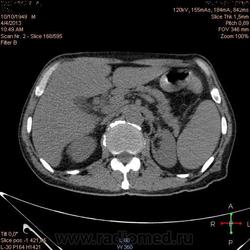

Здравствуйте, коллеги.Помогите разобраться.Пациент 1949 г беспокоять боли в животе , отсутствие аппетита, похудание .За неделю пожелтел, ослаблен.Нужно исключит кацер головки подж.железы.Анализы сегодня сдал еще не готовы.УЗИ зак увеличение л\узлов у ворот печени.Образов головки подж.железы ?На КТ жировой гепатоз.вроде головка подж железы не увеличены.

Мне надо исключить или поставить образование головки подж.железы.Хирурги ждут заключение, хотять оперировать.

А про билиарную гипертензию на УЗИ и КТ ничего не говорится?

Даже если вы пропустили малый рак панкреас, пациент умер не из-за него - желтуха не механическая, а, вероятней, паренхиматозная.